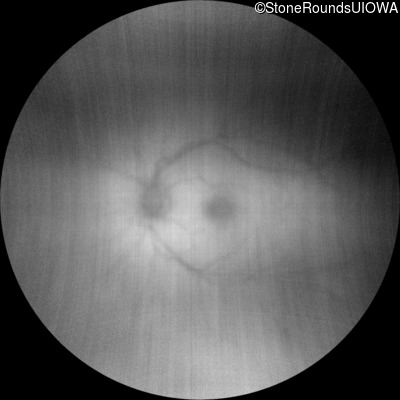

XL Retinoschisis (IIIB1)

Age at visit: 7 years

This 7 year old boy failed a vision screening test at his pediatrician 5 months ago.